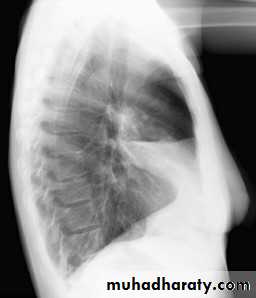

CXR of adult male ,PA and lateral views show:

Homogenus opacity in the left lower lobe triangular in shape

In the lateral view the density of the lower vertebrae is more than the upper vetebrae (abnormal)

important note>>> density of the upper spine is more than density of the lower spine